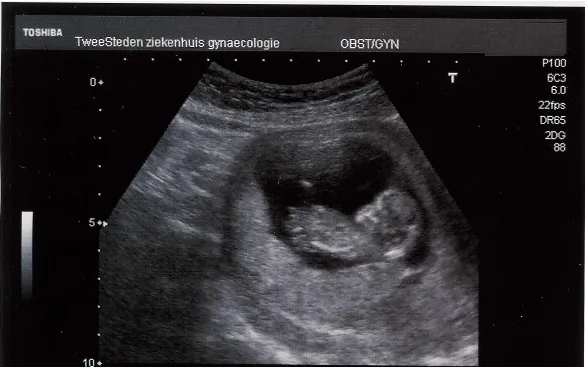

echo

CC BY-SA 3.0 / Hullie / Wikipedia

TILBURG - De Brabantse verloskundigen en ziekenhuizen streven ernaar om partners op korte termijn weer aanwezig te laten zijn tijdens de 20-weken echo. De eerstelijns echocentra en echoafdelingen van ziekenhuizen zullen met zwangeren communiceren per wanneer dit weer mogelijk is. Partners kunnen echter nog niet bij elk consult en bij elke echo aanwezig zijn. Ook is er nog geen extra persoon toegestaan bij bevallingen in het ziekenhuis.